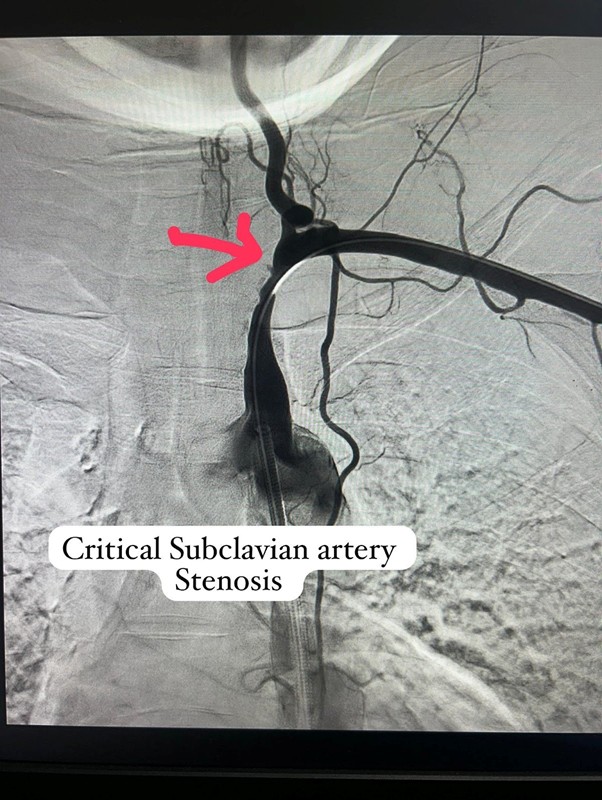

A young female patient with a prior history of stroke presented with a 100% thrombotic occlusion of the left subclavian artery, significantly compromising blood flow. She had previously been advised to undergo surgical intervention at another center. Upon presenting to Good Heart Clinic, Dr. Ingle conducted a comprehensive clinical assessment and opted for a carefully planned, patient-first approach.

After a few weeks of medical therapy, a repeat CT Angiography showed partial recanalization of the previously occluded subclavian artery, indicating a positive response to treatment. To further define the anatomy and plan intervention precisely, Digital Subtraction Angiography (DSA) was performed. Based on these findings, Dr. Ingle successfully carried out a subclavian artery angioplasty, restoring critical blood flow to the affected limb and reducing future neurological risk.